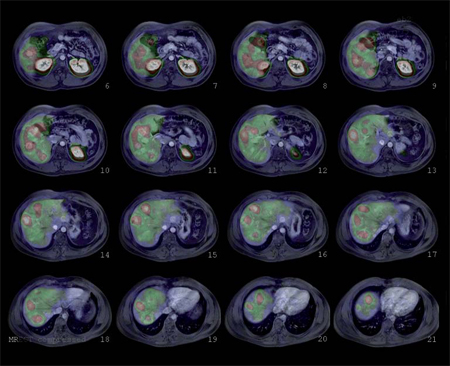

Tumores gastroenteropancreáticos

Este grupo (GEP) constituyen un grupo heterogéneo de tumores neuroendocrinos del estómago, páncreas e intestino. El más frecuente es el tumor carcinoide. El tratamiento primario es la cirugía aún en los pacientes con enfermedad metastásica, debido a que la resección parcial puede mejorar la calidad de vida, sobrevida y estado funcional. Las imágenes cumplen un papel importante para determinar la extensión de la enfermedad al inicio y en el seguimiento. Los estudios realizados con 111In pentatreotide muestran elevada sensibilidad para la detección de GEP a excepción del insulinoma. La sensibilidad para el gastrinoma metastásico, carcinoide y otros GEP son generalmente sobre 80% hasta 94%. La sensibilidad para la enfermedad metastásica tiende a ser superior a la de los tumores primarios (Figura 1) y en muchas ocasiones se encuentran lesiones no detectables por imágenes anatómicas. Utilizando Ga68 análogos de somatostatina se han obtenido excelentes resultados, con sensibilidades entre 82-100% (Figuras 2 y 3). El FDG tiene baja sensibilidad para la detección de estos tumores de lento crecimiento, bien diferenciados y bajo Ki-67, en cambio las imágenes con análogos de somatostatina presentan un patrón opuesto (Figura 4 y 5). Los tumores neuroendocrinos indiferenciados y agresivos presentan marcada avidez por la glucosa y pobre expresión de receptores de somatostatina y viceversa. Se ha visto que los pacientes con tumores con mayor expresión de Ki-67 evolucionan peor que aquellos con bajo Ki-6715. Los tumores neuroendocrinos que captan FDG tienen por lo tanto peor pronóstico16. En un estudio que comparó el rendimiento de cintigrafía con Octreoscan y FDG en pacientes con tumor carcinoide encontró que el 86% de los tumores primarios se localizaban con pentatreotide mientras que sólo el 57% con FDG. Pacientes con metástasis, el 69% fue positivo con el análogo de somatostatina, 47% con FDG y 56% con imágenes anatómicas17. Figuras similares se han obtenido con el uso de PET y Ga68análogos de somatostatina18,19.